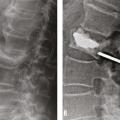

Dans la cyphoplastie, des ballonnets sont mis en place par voie transpédiculaire dans le corps vertébral fracturé, puis gonflés sous pression pour relever le plateau vertébral enfoncé et créer ainsi une cavité intracorporéale (fig. 2). Les ballonnets sont ensuite dégonflés et retirés et le ciment injecté à basse pression afin de remplir la cavité créée, ce qui diminue le risque de fuite extravertébrale de ciment. À côté de la cyphoplastie à ballonnets sont maintenant proposés de nombreux dispositifs de réexpansion vertébrale tels que des stents ou des « cricks » qui servent à repousser le plateau vertébral enfoncé mais sont laissés en place et « coulés » dans le ciment. Ils sont plus utilisés dans les fractures traumatiques ou malignes que dans l’ostéoporose. L’objectif de la cyphoplastie à ballonnets et de ces dispositifs est de réduire au moins partiellement l’angle de cyphose vertébrale qui est parfois important dans certaines fractures cunéiformes.